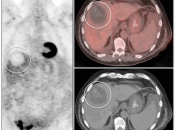

Radiofrequency Ablation of Liver Lesions

Although there is considerable variation in the recommended timing of PET/CT imaging after radiofrequency ablation of liver lesions, PET/CT has shown considerable utility for detecting recurrent/residual disease.

Some advocate post-procedure PET/CT imaging 24-48 hours after ablation to assure that the entire lesion has been fully treated (any remaining FDG uptake at this very early stage should represent residual active tumor, not post-procedural inflammation).

Later follow-up can then often performed, as clinically warranted (often at 3 and 6-months).

Benign Findings:

- Complete absence of metabolic activity in an ablated lesion is consistent with successful treatment.

- A homogeneous rim of well-defined peripheral hypermetabolic activity surrounding a non-avid hypodensity is presumed to represent post-ablation inflammatory changes.

The peripheral nature of this uptake is often best appreciated on the coronal images.

Recurrent/Residual Malignancy:

- Any nodular or focal uptake within or abutting the ablated lesion is highly suspicious for malignancy.